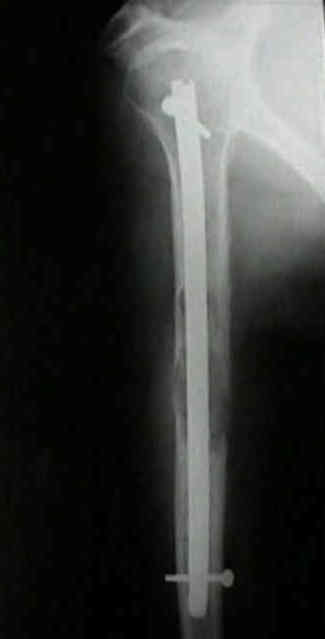

El enclavado endomedular constituye uno de los pilares fundamentales en el tratamiento de las fracturas patológicas y fracturas diafisarias del fémur y el húmero. Su principal objetivo es proporcionar una estabilización mecánica inmediata que permita controlar el dolor, facilitar la movilización precoz y mejorar la calidad de vida del paciente. Sin embargo, en el contexto oncológico, esta técnica conlleva riesgos específicos y consideraciones críticas que la diferencian sustancialmente de su aplicación en traumatología convencional. El error más grave y potencialmente catastrófico consiste en estabilizar con un clavo intramedular una lesión que en realidad corresponde a un sarcoma óseo primario no diagnosticado. Esta guía aborda los principios actuales, la técnica depurada y las medidas de seguridad obligatorias para un manejo seguro y eficaz.

El enclavado endomedular está indicado fundamentalmente para la estabilización de fracturas diafisarias completas o inminentes (fracturas pendientes) en huesos largos. En el contexto oncológico, su uso más frecuente es en pacientes con metástasis óseas, especialmente secundarias a tumores de mama, pulmón, próstata y riñón, donde proporciona una solución rápida y efectiva para restaurar la estabilidad mecánica.

- • Fractura patológica completa: Es el tratamiento de elección para fracturas diafisarias femorales y humerales, ya que permite la carga precoz y reduce la estancia hospitalaria.

- • Tipo de clavo: Para fracturas patológicas, se prefieren clavos de acerrojado estático (proximal y distal) para maximizar la estabilidad rotacional y axial. En lesiones muy extensas o con pérdida ósea importante, pueden utilizarse clavos especiales para metástasis que permiten inyectar cemento a través de perforaciones en el implante, añadiendo fijación adicional.

- • Extensión del clavo: El clavo debe abarcar todo el hueso afectado. Si existen metástasis en el cuello femoral o en el cóndilo, se deben usar clavos largos (cervico‑céfalo‑trocantéricos o largos retrógrados) que estabilicen toda la longitud del fémur.

3) Enclavado endomedular humeral: abordajes anterógrado y retrógrado

El enclavado humeral es una excelente opción para fracturas diafisarias patológicas, ya que permite una estabilización inmediata con menor agresión quirúrgica que el abordaje abierto con placa. Sin embargo, presenta desafíos únicos relacionados con la anatomía del hombro y la proximidad del nervio radial. La elección entre abordaje anterógrado y retrógrado debe basarse en la localización de la fractura, el estado del manguito rotador y las expectativas funcionales del paciente.